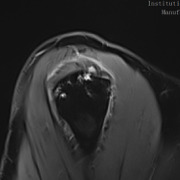

The MRI revealed an anterior full-thickness supraspinatus tear from the origin with mild retraction and moderate delamination. Fluid signal was seen within the mid-substance of the supraspinatus tendon medial to the location of full thickness tear. Subchondral cystic changes in the greater tuberosity were also observed at the insertion site. (Figures 4 & 5)